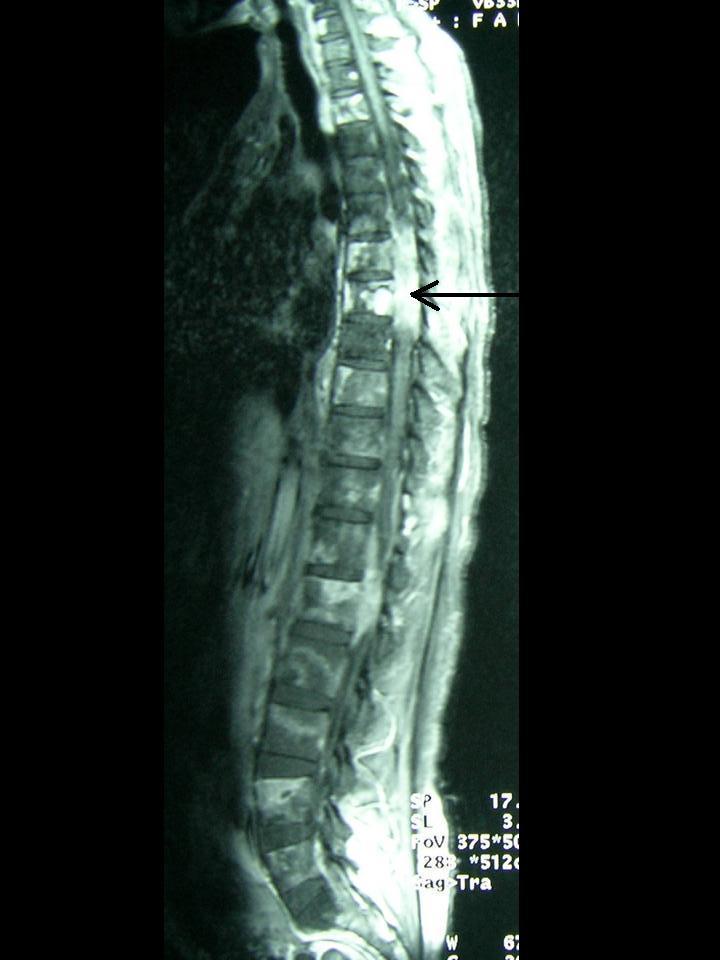

Glioblastoma multiforme (GBM) is the most aggressive form of primary brain tumours known collectively as gliomas. Gliomas are graded by their microscopic appearance. As a rule, their behaviour can be predicted from histology: Grade I (pilocytic astrocytomas) and Grade II (benign astrocytomas) tumours are of low grade and grow slowly over many years. Grade IV tumours (GBM) are the most aggressive and, unfortunately, also the most common in humans, growing rapidly, invading and altering brain function. These tumours arise from the supporting glial cells of the brain during childhood and in adulthood.These growths do not spread throughout the body like other forms of cancer, but cause symptoms by invading the brain. Untreated GBMs are rapidly lethal. Most patients with GBM die of their disease in less than a year and none have long term survival.Extracranial metastases from GBM are extremely rare, with a reported frequency of only 0.44% because of the absence of lymphatics in the brain and the difficulty of tumours to penetrate blood vessels. A case of glioblastoma multiforme with the rare features of extensive liver and bone metastases is presented in this paper.

多形性胶质母细胞瘤(GBM)是统称为胶质瘤的原发性脑肿瘤中最具侵袭性的类型。胶质瘤根据其显微镜下的表现进行分级。通常,其行为可从组织学上预测:I级(毛细胞型星形细胞瘤)和II级(良性星形细胞瘤)肿瘤为低级别,多年来生长缓慢。IV级肿瘤(GBM)最具侵袭性,不幸的是,在人类中也最常见,生长迅速,侵袭并改变脑功能。这些肿瘤在儿童期和成年期由大脑的支持性胶质细胞产生。这些肿瘤不像其他形式的癌症那样扩散到全身,而是通过侵袭大脑引起症状。未经治疗的GBM迅速致命。大多数GBM患者在不到一年的时间内死于疾病,无一例长期存活。由于大脑中缺乏淋巴管以及肿瘤穿透血管困难,GBM的颅外转移极为罕见,报告的发生率仅为0.44%。本文介绍了一例具有广泛肝转移和骨转移罕见特征的多形性胶质母细胞瘤病例。